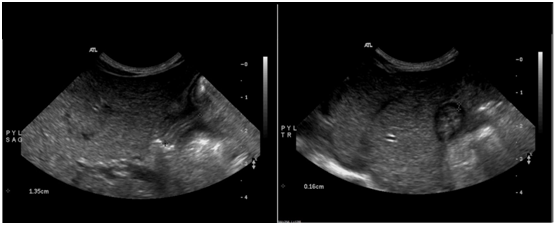

He remained relatively asymptomatic until DOL 7 after which he restarted with episodes of post-prandial non-bilious vomiting 4-5times a day, which were occasionally projectile. An ultrasonography of the abdomen on DOL 10 revealed a high normal pyloric canal length (PCL) of 14mm and a normal pyloric muscle thickness (PMT) of 2mm (Figure 1). Post prandial transmission of intraluminal content through the pylorus was mildly delayed. The radiological findings were deemed inconclusive of pyloric stenosis. Formula and breast milk were thickened. The infant began to arch his back and cry after feedings whilst he demanded frequent feeds and fed vigorously. Famotidine was started for a presumptive diagnosis of gastro esophagral reflux on DOL 11. Occasional intermittent non-bilious and projectile vomiting persisted; however, electrolytes remained normal. On physical examination visible post prandial gastric peristalsis was noted to occur starting during the first week, which became more common with increasing chronological age, but olive mass was not palpated. An upper GI series was done on DOL 17, which demonstrated holdup of ingested contrast within the stomach, though some oral contrast was visualized in the small bowel. Gastroesophageal reflux was noted up to the level of the clavicles. At this stage, evolving pyloric stenosis was suspected and a repeat abdominal ultrasonography was performed on DOL 20. Longitudinal images by sonogram demonstrated a PCL of 17mm and PMT of 3.5mm consistent with IHPS, along with a pylorus that did not distend with administration of water into the stomach (Figure 2).

Figure 2 Results of ultrasonography studies performed on day of life 20.